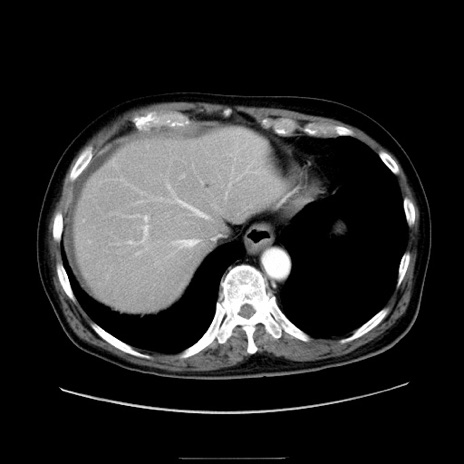

症例30(横断像)

【症例】80歳代男性

【現病歴】約6時間前から臍下部痛が出現。次第に腹部膨隆・背部痛も生じてきたため来院。背部痛の場所は変化しない。

【身体所見】意識清明、BT 36.3℃、BP  131/87mmHg、P 87bpm、SpO2 100%(RA)、臍周囲自発痛・圧痛あり、反跳痛なし、自発痛部位に一致して板状硬あり、腹部膨隆、腸雑音減弱、CVA tenderness両側陰性。

【データ】WBC 19600、CRP 0.33